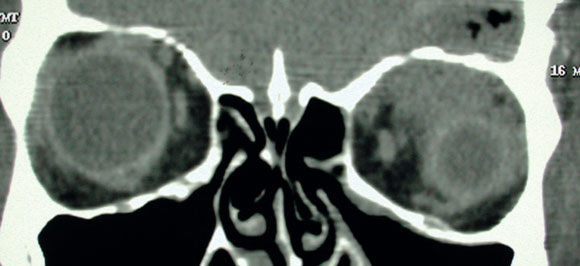

Non-contrast computed tomography (CT) of the brain revealed two minute areas of high density in the left frontal lobe, interpreted as evidence of early infection. CT of the orbits revealed left-sided swelling of the subcutaneous soft tissue, interpreted as preseptal cellulitis. A fracture of the left orbital roof was also noted adjacent to a superior orbital phlegmon (Box 1A).

However, as the cerebrospinal fluid appeared normal on microscopy and biochemical examination and showed no growth on culture, the initial diagnosis was questioned. Magnetic resonance imaging of the brain and orbits was performed the day after presentation. This showed a 5 cm tract extending obliquely from the roof of the left orbit into the white matter of the left frontal lobe, associated with a fracture of the orbital plate of the frontal bone (Box 1B). Inflammatory changes, presumed infective, were noted superiorly within the left orbit, resulting in proptosis.

It was concluded that the patient had incurred a penetrating injury of the left orbit entering through the nasal conjunctiva and extending superiorly to the globe, through the orbital plate of the left frontal bone, and into the frontal lobe.